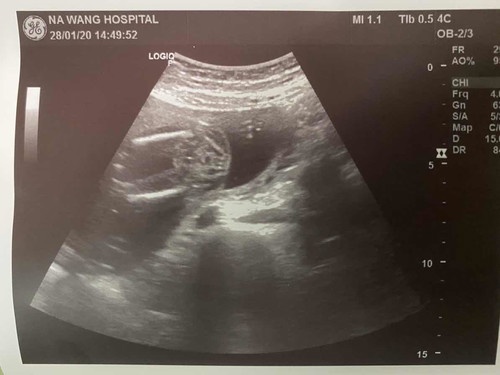

มีใครดูออกไหมคะว่าเพศไหน

19weeks+5 คุณหมอยังดูไม่ออกเลยค่ะว่าเพศไหน อิแม่รอบุ้นใจจิขาดแน้วว

ไม่ค่อยชัดค่ะ มีแนวโน้มผู้หญิง รอน้องโตกว่านี้ค่อยซาวใหม่ต่ะ

เหมือนผญ.นะคะ แต่ก็อาจคลาดเคลื่อนได้

หญิงแน่เลยค่ะ ไม่มีแหลมๆ

คิดว่าผญ. เพราะคล้ายๆกัน

น่าจะผู้หญิงน่ะค่ะ

น่าจะเพศหญิงค่ะ

คิดว่าหญิงคะ